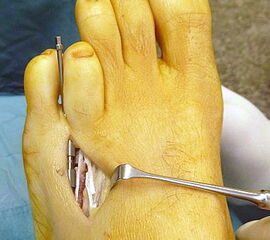

Das im Folgenden vorgestellte Operationsverfahren beschreibt die Kallusdistraktion von Metatarsalia nach den Prinzipien von Ilisarov 21 unter Verwendung eines internen, winkelstabilen Titan-Minifixateur (Klauser 2009). Der interne Distraktor ermöglicht während der Distraktions- und der Durchbauungsphase aufgrund seiner hohen Stabilität je nach Modell (18 mm, 23 mm) eine Verlängerung von bis zu 25 mm. Nach interner Anlage des Minifixateurs, meist lateral, kann über eine kontinuierliche Kallusdistraktion der Metatarsalebogen unter frühzeitiger Mobilisation im Gips oder Short-Walker rekonstruiert werden 15. Über einen interdigital und transcutan ausgeleiteten Aktivatorstab wird die Distraktion vom Patienten selber täglich morgens und abends durchgeführt. Zusätzlich vorliegende Strahlpathologien, wie zum Beispiel eine verkürzte Strecksehne oder ein kontraktes Metatarsophalangealgelenk können im Rahmen der Erstoperation ebenso therapiert werden wie z.B. ein Hallux valgus, ein Hallux valgus interphalangeus und/oder ein Digitus quintus varus (Klauser 2009). Nach Rekonstruktion des Metatarsalebogens wird in einem zweiten, kleinen Eingriff der Aktivatorstab über eine Spezialpinzette diskonnektiert und entfernt, wobei der Distraktor als interne Fixation belassen wird. Die Entfernung des Distraktors erfolgt in der Regel nach 9 – 12 Monaten, da es sich meist um angeborene kindliche Fehlbildungen handelt (Brachymetatarsie) und eine operative Intervention frühzeitig im Kindesalter erfolgen sollte (Klauser 2009).

• Zweiter Eingriff: Diskonnektieren des transcutan ausgeleiteten Aktivator, falls möglich, über eine kleine Inzision von 1,5 bis 2 cm, in der Regel jedoch über Eröffnen der alten Schnittführung mit ggf. Strecksehnenverlängerung und erneutem Grundgelenk-Release sowie ggf. Ausleiten einer Penroselasche oder einer Gentamycin-Palacos-Minikette.